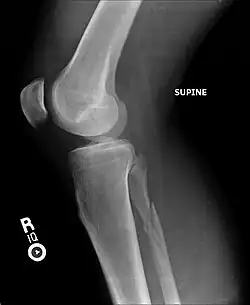

Radiograph showing a Maisonneuve fracture of the proximal fibula

The Maisonneuve fracture is a spiral fracture of the proximal third of the fibula associated with a tear of the distal tibiofibular syndesmosis and the interosseous membrane. There is an associated fracture of the medial malleolus or rupture of the deep deltoid ligament of the ankle. This type of injury can be difficult to detect.[1][2]